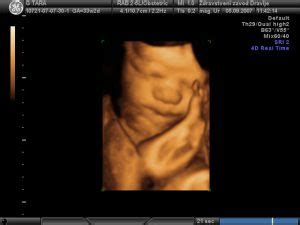

Ultrazvočna (UZ) preiskava v tem zgodnjem obdobju omogoča potrditev lege nosečnosti (v maternici ali zunaj nje), določitev števila plodov in oceno njihove vitalnosti. Z meritvami velikosti ploda se lahko določi pričakovani datum poroda. V tem času je natančnejša ocena razvoja ploda še omejena, saj so vidni le osnovni obrisi, kot je glava in nakazane okončine. Od 6. tedna dalje je mogoče opazovati tudi plodov srčni utrip. Če nosečnica pride na prvi pregled pred 8. tednom, se vsi nadaljnji pregledi izvajajo do 12. tedna nosečnosti.

- Morfološki pregled ploda: Ena najpomembnejših preiskav poteka med 20. in 22. tednom nosečnosti. Namenjena je natančni oceni razvoja plodovih organov in struktur. Cilj je potrditi normalni razvoj ali odkriti večje razvojne nepravilnosti ter tako imenovane "mehke označevalce", ki povečajo tveganje za prisotnost kromosomskih napak. V tem obdobju je razvoj večine organov že zaključen, kar omogoča z veliko verjetnostjo napoved rojstva zdravega otroka. Izjema so pljuča in možgani, katerih razvoj se nadaljuje tudi po rojstvu, zato je nevrološka ocena v tem času manj zanesljiva.

Oddelki za perinatologijo, kot je tisti na Kliniki za ginekologijo in perinatologijo, se preoblikujejo v centre terciarne ravni, ki obravnavajo nosečnice iz širših regij. Ti oddelki so opremljeni z najsodobnejšo tehnologijo za prenatalno diagnostiko, vključno s 3D/4D ultrazvokom. Poleg tega nudijo tudi možnost zunanjega obrata ploda v primeru medenične vstave, upoštevajo porodni načrt nosečnice ter omogočajo prisotnost partnerja pri porodu. Po porodu, ne glede na način poroda, nudijo podporo pri spoznavanju nege otroka, spodbujajo dojenje in zagotavljajo novorojencu prijazno okolje. Odsek za neonatologijo skrbi za prezgodaj rojene in kritično bolne novorojence.